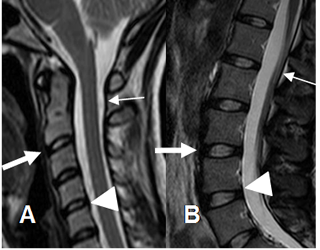

Los ligamentos se aprecian como bandas delgadas e hipointensas en todas las secuencias, mejor evaluados en secuencias sagitales de T2. (6, 7). (Fig 15).

Fig 15. Ligamentos normales.

A: RM cervical sagital en T2 y B: RM lumbar sagital en T2. Ligamento vertebral anterior (Flecha gruesa), ligamento vertebral posterior (Punta de flecha) y ligamento amarillo. (Flecha delgada).